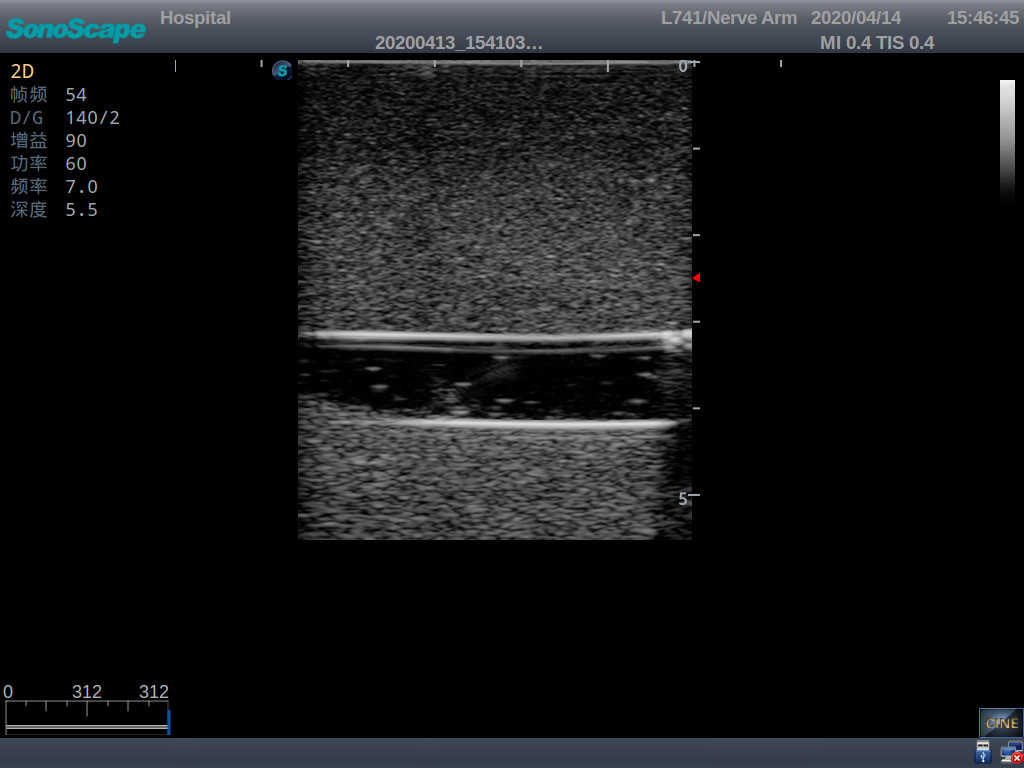

PICC Ultrasound Training Model

Model TYE1510.1

1)   Made of high molecular polymer ultrasound material, close to the real skin

2)   It can be used by real ultrasound machines

3)   Clear and real images of the tissues and organs (basilic vein and superior vena cava)